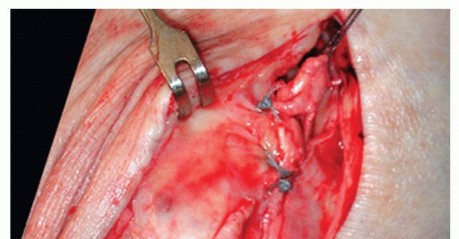

- Complete Acute Rupture

Because the rupture is mostly situated at the proximal end of the deltoid ligament (TECH FIG 3),

reattachment to the medial malleolus is achieved by interosseous sutures; a bony anchor can also be used for refixation to the bone.6 - Chronic Rupture of the Superficial Deltoid Ligament

- TECH FIG 3 • Acute deltoid rupture. This 28-year-old soccer player sustained a valgus trauma, causing an acute giving way of the foot. A. MR imaging reveals complete disruption of the ligament close to its proximal insertion to the medial malleolus. B. Surgical exploration confirms complete disruption of the deltoid ligament, although the posterior tibial tendon remained intact.